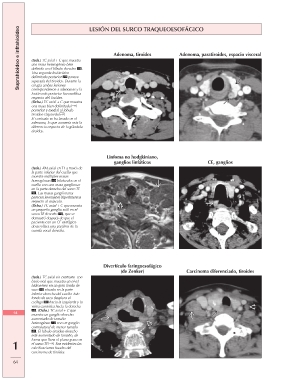

Suprahioideo e infrahioideo LESIÓN DEL SURCO TRAQUEOESOFÁGICO

Adenoma, tiroides Adenoma, paratiroides, espacio visceral

(Izda.) TC axial + C que muestra

una masa heterogénea bien

definida en el lóbulo derecho .

Una segunda lesión bien

delimitada posterior parece

separada del tiroides. Durante la

cirugía ambas lesiones

correspondieron a adenomas y la

lesión más posterior fue exofítica

respecto del tiroides.

(Dcha.) TC axial + C que muestra

una masa bien delimitada

posterior y medial al lóbulo

tiroideo izquierdo .

El contraste se ha lavado en el

adenoma, lo que aumenta más la

diferencia respecto de la glándula

tiroides.

Linfoma no hodgkiniano, CE, ganglios

ganglios linfáticos

(Izda.) RM axial en T1 a través de

la parte inferior del cuello que

muestra múltiples masas

homogéneas bilaterales en el

cuello con una masa ganglionar

en la parte derecha del surco TE

. Las masas ganglionares

parecen levemente hiperintensas

respecto al músculo.

un pequeño ganglio sutil en el

surco TE derecho , que se

demostró después de que el

paciente con un CE esofágico

desarrollara una parálisis de la

cuerda vocal derecha.

Divertículo faringoesofágico Carcinoma diferenciado, tiroides

(de Zenker)

(Izda.) TC axial sin contraste con

bario oral que muestra un nivel

hidroaéreo en un gran fondo de

saco situado en la parte

inferior derecha del cuello. Este

fondo de saco desplaza el

esófago hacia la izquierda y la

vaina carotídea hacia la derecha

. (Dcha.) TC axial + C que

64 muestra un ganglio derecho

aumentado de tamaño

heterogéneo con un ganglio

contralateral de menor tamaño

. El lóbulo tiroideo derecho

está aumentado de tamaño, de

1 forma que llena el plano graso en

el surco TE . Son evidentes las

calcificaciones focales del

carcinoma de tiroides.